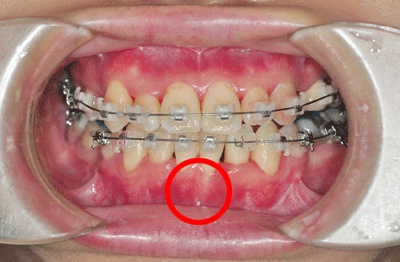

참고로 이날 찍은 치아 정면 사진을 보면

잇몸이 전보다 더 내려간 것을 볼 수 있음.

내 잇몸….

8월에 찍은 사진. 그 사이에 잇몸뼈가 더 얼굴을 내밀었다.

▼ ▼아랫니▼ ▼